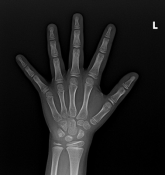

骨骺线是骨骺与干骺端之间的软骨,又称为“骺板”或“生长板”,在儿童腕掌指骨及膝关节的X光片上表现为一条较宽的透光带,它的闭合程度直接关系到孩子还有多少长高空间。

1.骨骺线未闭合:软骨还能继续骨化,孩子仍有很大长高潜力,这是正常生长的“黄金期”。

2.骨骺线部分闭合:软骨逐渐减少,生长速度放缓,剩余长高空间有限(通常每年增长不超过2-3cm)。

3.骨骺线完全闭合:骨骼停止生长,身高基本定型(仅脊柱可能有1-2cm弹性增长)。